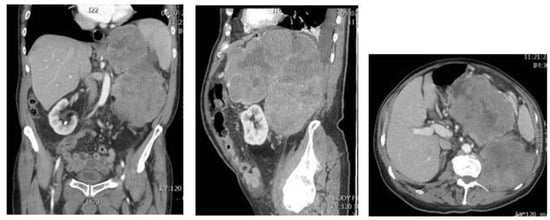

Dedifferentiated liposarcoma (DDL) is defined as the transition of WDL/ATL towards nonlipogenic sarcoma, either in the primary tumor or in a recurrence. The well-differentiated component can be absent. A total of 90% of DDL present de novo, +/− 10% of WDL/ATL dedifferentiate into DDL. Patients are most often older than 45 years. The retroperitoneum is the most frequent site (80%), and DDL is the most frequent retroperitoneal sarcoma (Figure 6). Other sites are the deep soft tissue of the extremities, the funiculus spermaticus/paratesticulum and mediastinum. The transition to the nonlipogenic sarcoma is usually abrupt and the latter most often looks like undifferentiated pleomorphic or spindle cell sarcoma, but myxoid sarcoma-like pictures, or low grade desmoid-like areas, can be seen as well (Figure 7 and Figure 8). Heterologous differentiation is present in up to 10%, myogenic (leiomyo-, or rhabdomyosarcoma) being most frequent, followed by osteo- or chondrosarcoma-like phenotypes [,]. A peculiar type is the DDL with meningothelial-like whorls and metaplastic bone formation, typically seen in the retroperitoneum (Figure 9) []. In the past, an inflammatory type of malignant fibrous histiocytoma, rich in neutrophils and also occurring in the retroperitoneum, was described. This tumor represents another phenotype of DDL []. In fact, DDL can mimic any type of sarcoma and MDM2 immunohistochemistry/FISH should be part of the panel of tests in any sarcoma occurring at any site, certainly if it is undifferentiated and pleomorphic. Thus, if one is confronted with an undifferentiated pleomorphic or spindle cell sarcoma, even if there is virtually no fat, the finding of MDM2 expression/amplification will indicate that it concerns a DDL []. An interesting but unusual form of dedifferentiation is the so-called homologous lipogenic dedifferentiation, which is characterized by big atypical lipoblasts, exactly as seen in pleomorphic liposarcoma []. MDM2 expression usually is very prominent in the dedifferentiated area as opposed to the well-differentiated part (Figure 7). Once dedifferentiation is present, the tumor gains metastatic potential but is less aggressive than other pleomorphic sarcomas. Recurrence is seen in at least 40% of cases, metastatic rates vary between 15 and 30% and tumor-related death is +/− 28% at 5-year follow-up. This figure is without any doubt much higher at 10 to 20 years []. Recent studies indicate that high grade dedifferentiation and the presence of myogenic (particularly rhabdomyoblastic) dedifferentiation correlate with a worse prognosis [,,]. As in WDL/ATL, complete surgical resection is the mainstay of treatment. DDL also harbors high level amplifications of 12q14-15, including the MDM2 and CDK4 genes. The degree of MDM2 amplification might affect clinical outcome, although prospective studies are needed to objectivate this finding []. As opposed to WDL/ATL, DDL shows other genetic changes, as 6q23 and 1p32 co-amplifications. In this respect, JUN (1p32.2) is of interest since its amplification is probably involved in the progression from WDL/ATL to DDL. Another feature that favors dedifferentiation might be the loss of HMGA2 overexpression, which is frequent in DDL []. A recent study on the integrated exome and RNA sequencing of 115 DDLs showed elegantly that gains of several somatic copy-number alternations and chromosomal rearrangements, including the DNM3OS-fusion genes and the loss of G0S2 and DGAT2, contribute to the cell cycle progression and impairment of adipogenesis [].

Figure 6.

MRI pictures of a big retroperitoneal tumor in an 82-years-old male patient.